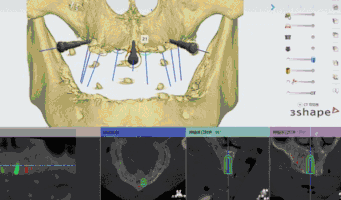

精彩案例: